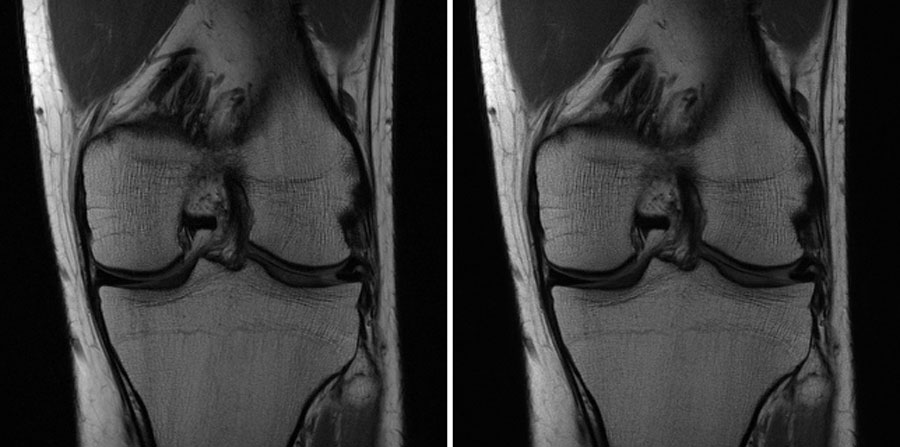

MRI scan

At left, raw data from an MRI. At right, what a typical image of a knee, created using sufficient data, looks like. Facebook / NYU School of Medicine

Gina Ciavarra is sitting in a dark room at NYU Langone Health in Manhattan. It’s a reading room, a space for radiologists like her to examine X-ray and MRI scans. The monitors in front of her display grayscale images of a de-identified patient’s knee, and in them she detects one key problem: a torn ACL. “This is definitely abnormal,” Ciavarra explains.

But there’s another evaluation that Ciavarra must make, in addition to scanning the swirls of bone, ligaments, fat, cartilage, and tendons for problems like tears or arthritis. Was this particular knee scan created by artificial intelligence, or did it emerge from an MRI machine the traditional way? “My gut says it’s AI,” she says, without certainty. “It just looks a little blurry.”